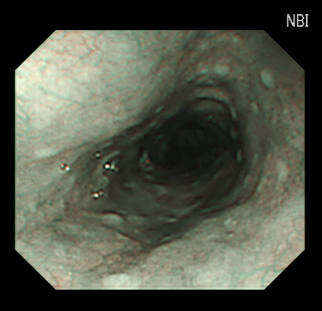

NBI画像:食道

(Narrow Band Imaging)狭帯域光観察